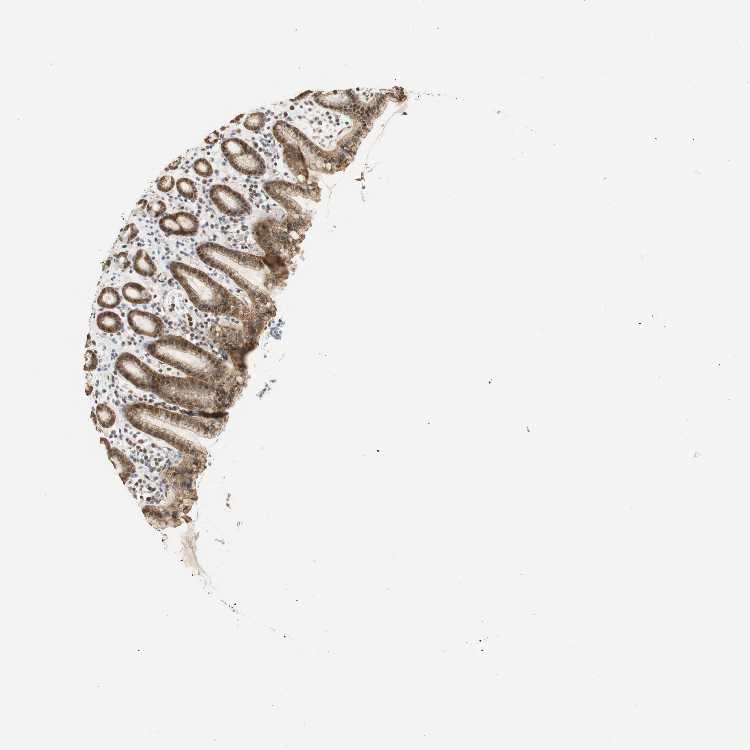

STOMACH 1 - Antibody stainingi

Antibody staining in the annotated cell types in the current human tissue is reported as not detected, low, medium, or high, based on conventional immunohistochemistry profiling in selected tissues. This score is based on the combination of the staining intensity and fraction of stained cells.

Each image is clickable and will lead to virtual microscopy that enables deeper exploration of all samples and also displays staining intensity scores, fraction scores and subcellular localization as well as patient and tissue information for each sample.

Antibody HPA044487Antibody CAB004656

Glandular cells HighHigh